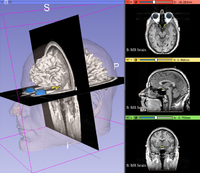

Data Loading and 3D Visualization

• Slicer 4.10

• The Data loading and visualization (pptx) course guides through the basics of loading and viewing volumes and 3D models in Slicer 4.10.

• Author: Csaba Pinter

• Modules: Welcome to Slicer, Data, Volume Rendering, Models.

• Audience: End-users

• Based on Slicer 4.9

• Compatible with Slicer 4.10.1

• The 3DVisualization dataset contains an MR scan and a series of 3D models of the brain.